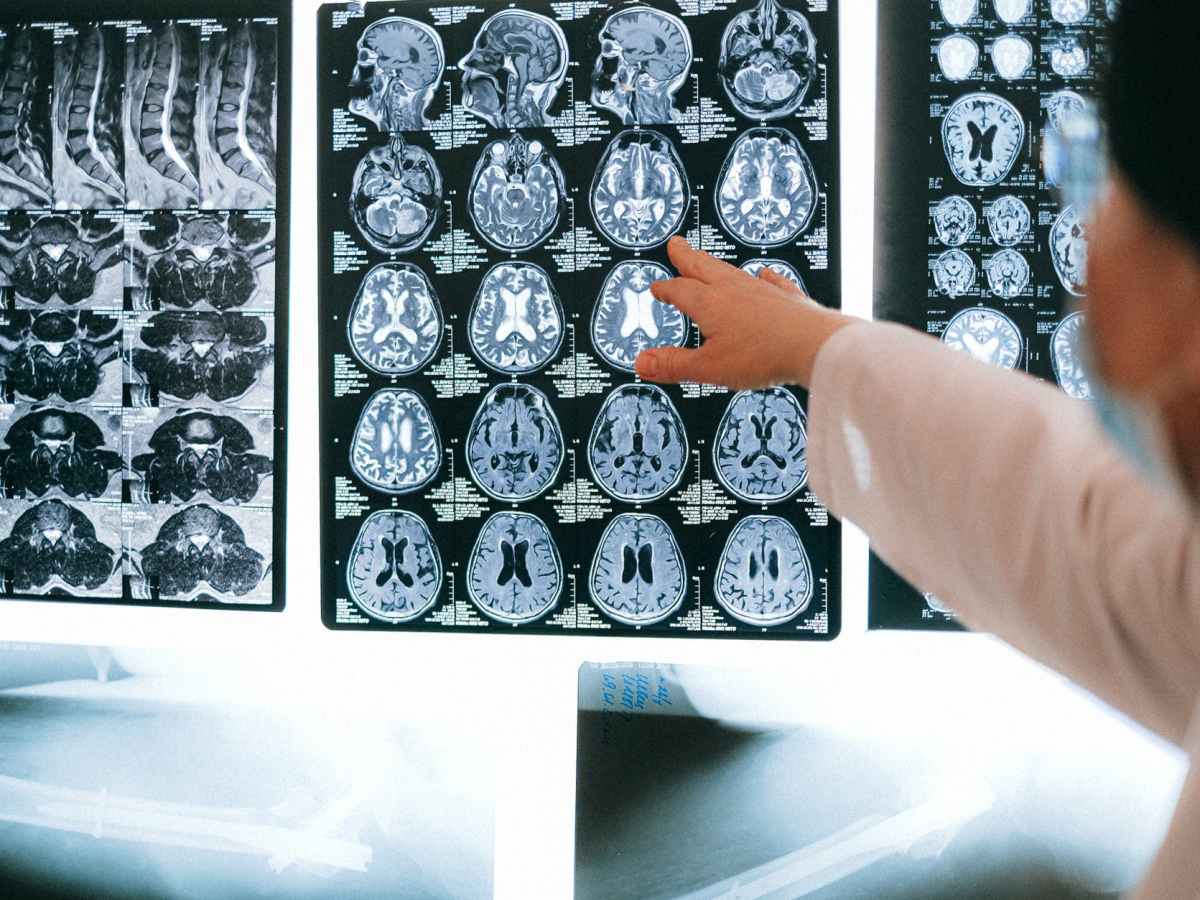

continua a leggereStrutture cerebrali coinvolte nella memoria

I ricordi non sono conservati in aree cerebrali specifiche. Gli elementi visivi sono codificati nelle…